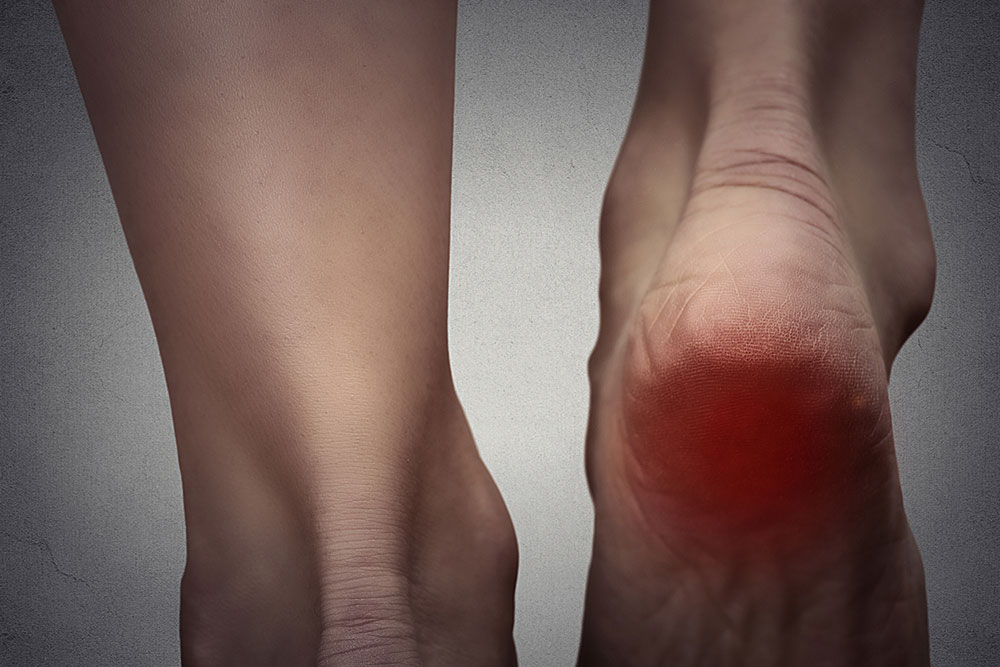

Heel spurs cause bony growths to prop out from the bottom of the heel. It makes walking extremely difficult and you must seek immediate treatment for the same. Buy customised shoes with heel padding and additional foot space to combat the pain and provide for additional comfort. You may or may not experience its symptoms initially. The condition is caused due to the build-up of calcium on the underside of the heel bone and the pain usually kicks in only months after the build-up begins.